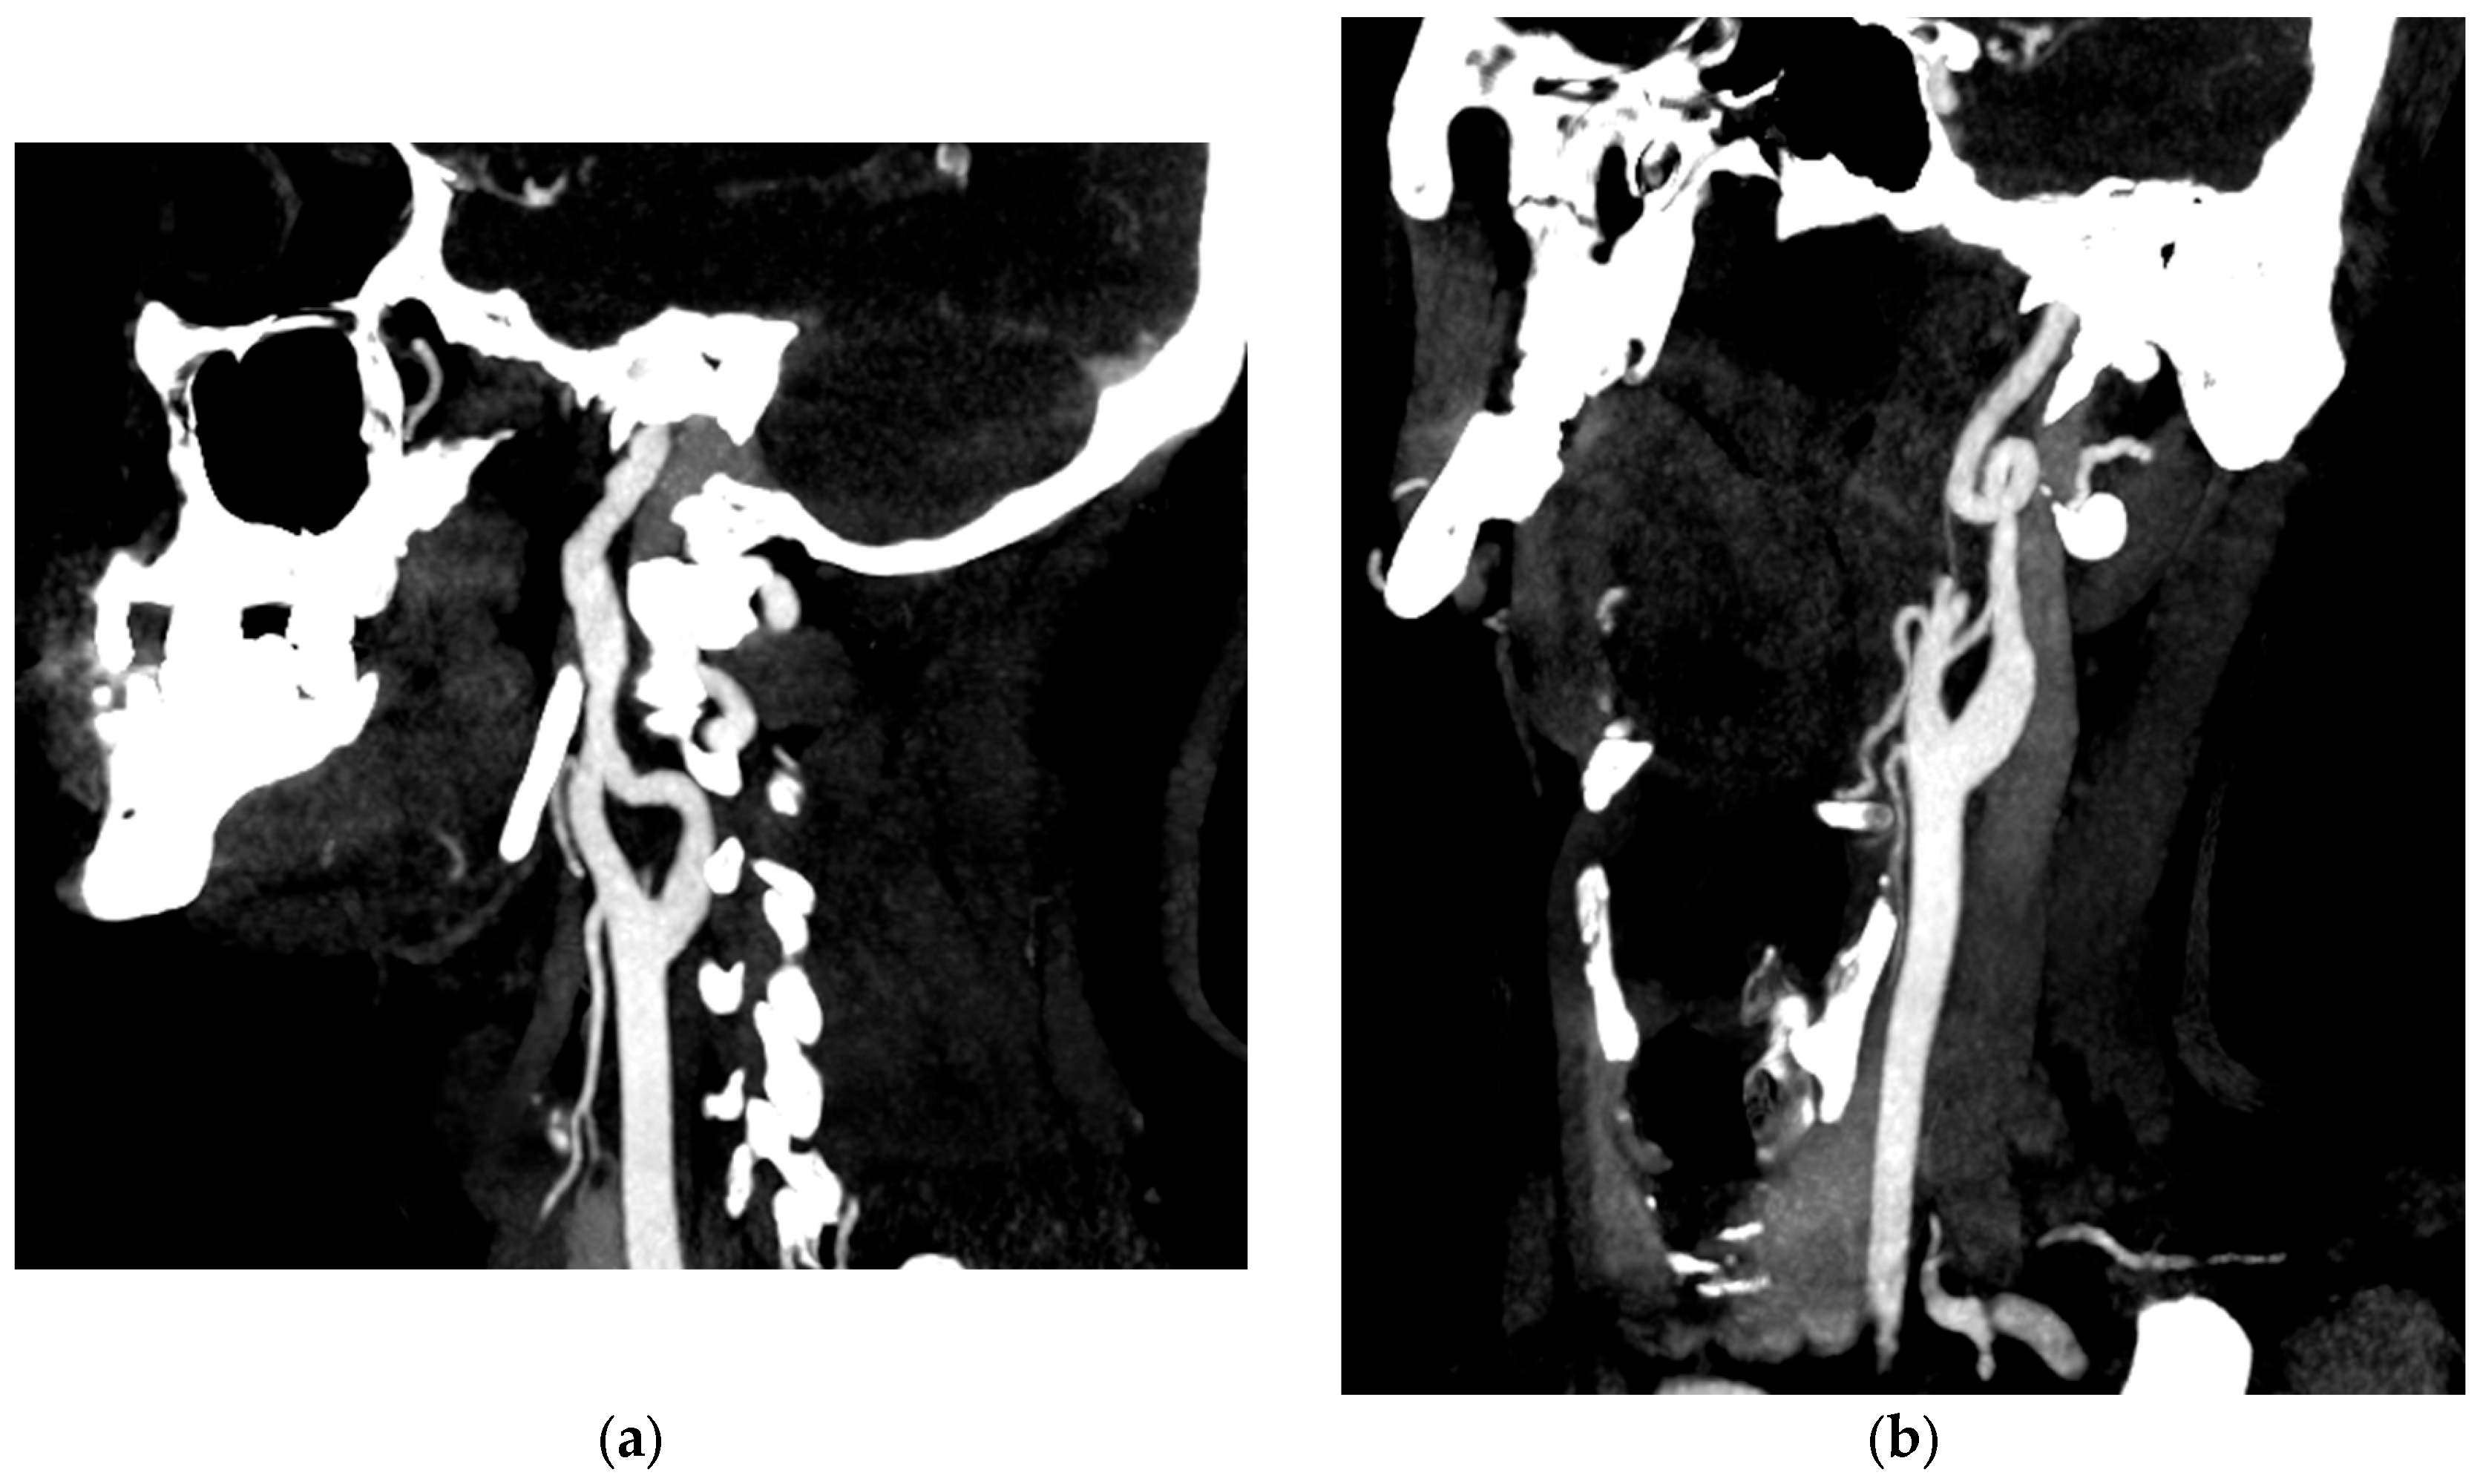

Etiologically, this patient presented with type A aortic dissection due to a pathological aortic aneurysm before the age of 40 years. There was no associated aortic bicuspidation or significant family history. However, review of the original CTA revealed additional medium calibre arterial anomalies. Ectasia was observed in the right vertebral artery (measured at 7.4 mm) and bilateral common iliac arteries (measured at 16 mm). Arterial tortuosity of the internal carotid artery and plication of the distal left internal carotid artery were also noted (Figure 6). We therefore decided to carry out a gene panel analysis even though there was no phenotypic evidence of Marfan syndrome or vascular Ehlers–Danlos syndrome.

Figure 6.

Angioscan of the supra-aortic trunks showing an irregular appearance of the right internal carotid artery (a) and a complete loop of the left internal carotid artery (b) in its pre-petrous portion.